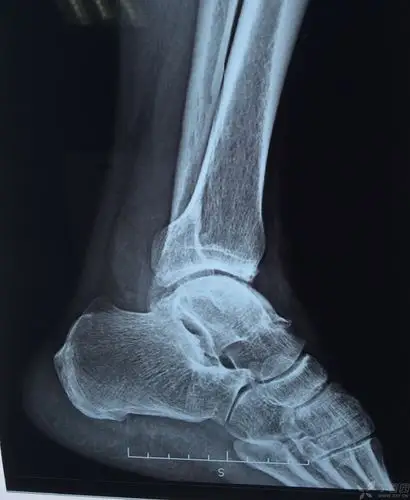

这是一个典型的踝部扭伤导致距腓前韧带损伤病历损伤

一例踝关节骨性关节炎并踝内翻,大家看看